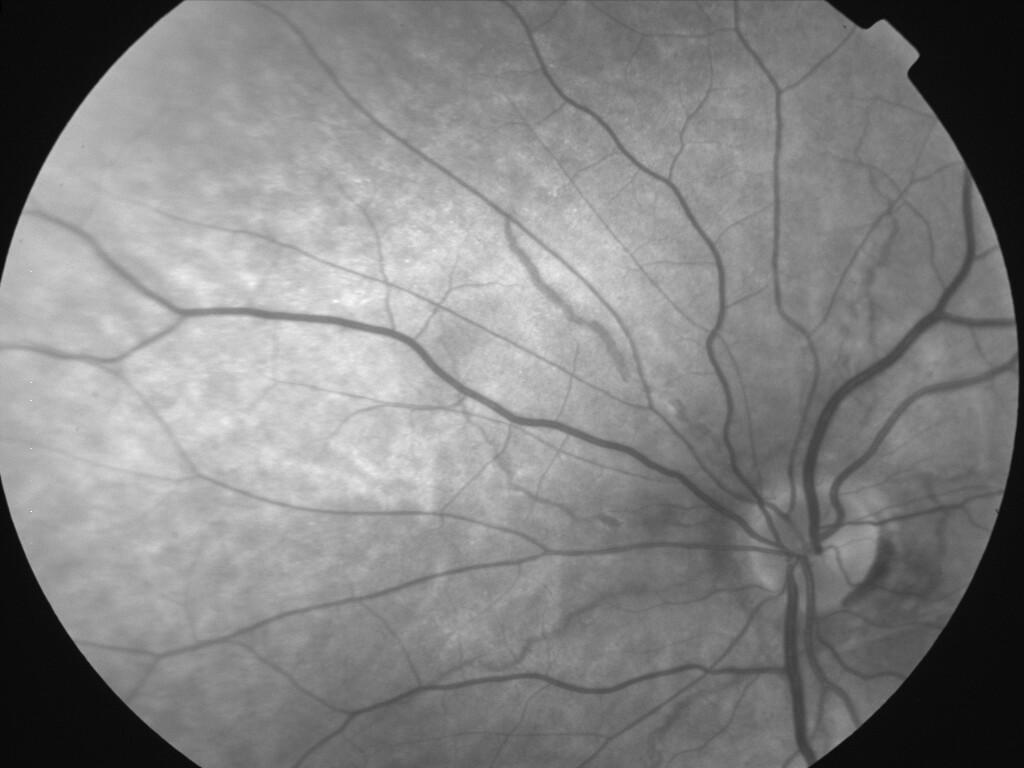

ASSOCIATION STRIES ANGIOIDES ET DYSROPHIE MACULAIRE RETICULEE

NEOVASCULARISATION